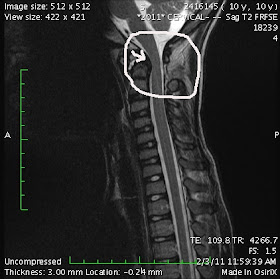

Here are pictures from Axel's MRI done a couple weeks ago. I put an arrow to the problem areas. It is important to remember when looking at these that Axel did not have one single symptom!!!! As his surgeon put it, he was "one bad cough away from catastrophic injury".

This first picture shows a couple of things. First, the arrow points to where the C1 vertebra is pushing against the spinal cord. Also, you can see on the front (left) side of the cord, between the C2 and C3 vertebrae, the disk looks different that the disks between the other vertebrae. That's because it doesn't have enough fluid in it to provide a cushion between the two vertebrae.

This pictures shows the Cerebrospinal Fluid (CSF) that surrounds the spinal cord. It is the white area around the cord. You can see where the arrow is how the CSF fluid is being blocked from getting to the brain. Thankfully it can also get to the brain on the back side of the spinal cord as well. Also, the spinal cord itself is more narrow in that area because of the movement of the C1 vertebrae.